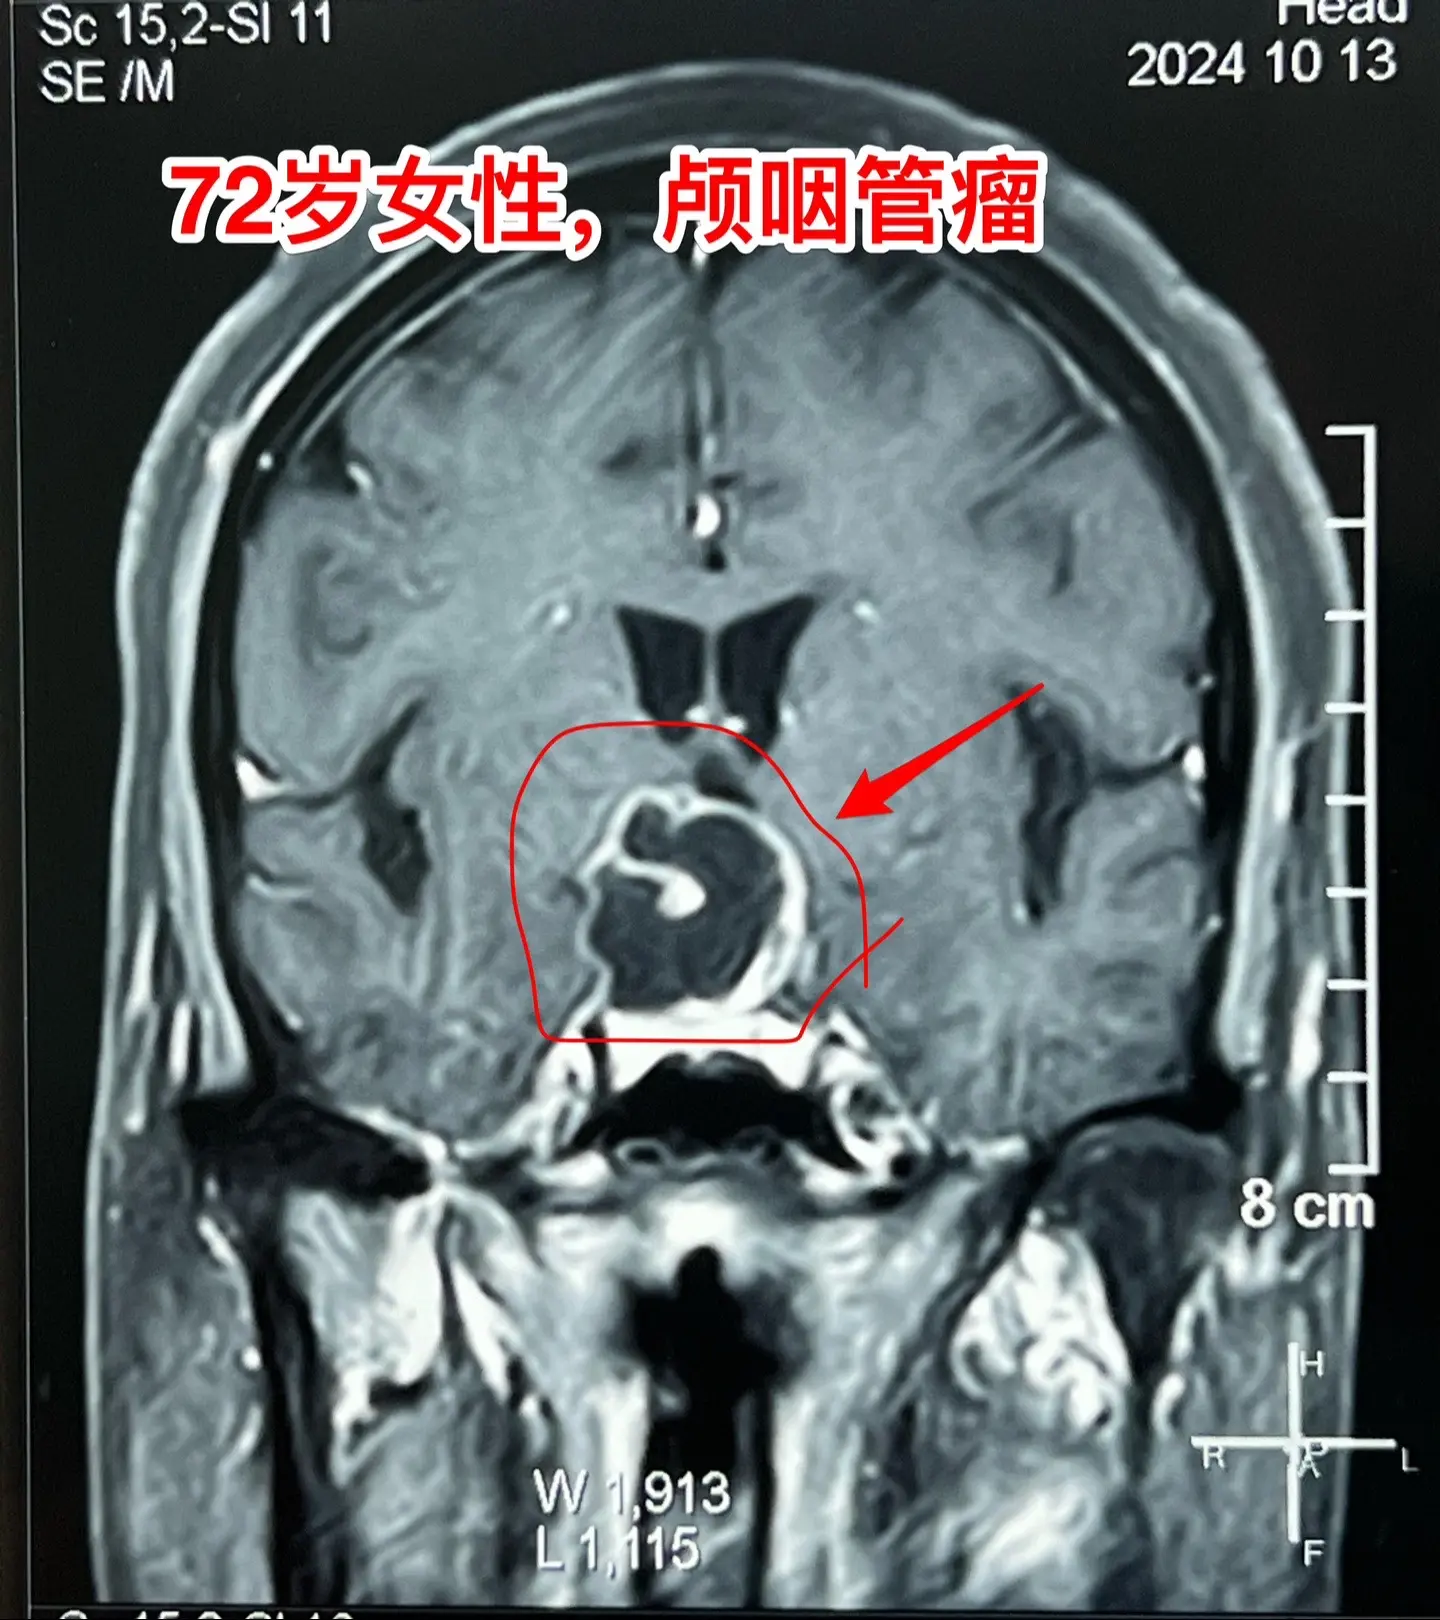

颅咽管瘤不单单是小孩子得的病!很多人认为颅咽管瘤是小孩子得的病,其实各个年龄段的人都可以患颅咽管瘤,我见过的颅咽管瘤病人年龄跨度从不到一岁到八十多岁! 相对而言,小孩子群体中(小于15岁)颅咽管瘤的发生率比较高! 这个72岁的山西晋城市老人在古稀之年患上了颅咽管瘤,病理报告是乳头型颅咽管瘤。10月25日在我科作了手术,11月13日出院。 老人在住院前胃肠功能不好,经常腹胀、消化不良。手术后也是经常感觉腹胀、食欲不振,身体康复过程相对比较缓慢。 老年人一般来说都伴有老年性疾病,比如糖尿病、高血压病、高脂血症、动脉硬化,身体大脏器机能下降,所以老年人患颅咽管瘤,作手术后恢复会比较慢,出意外的风险会增加,尤其是血管方面的并发症会增加,比如深静脉血栓、心肌梗死等。